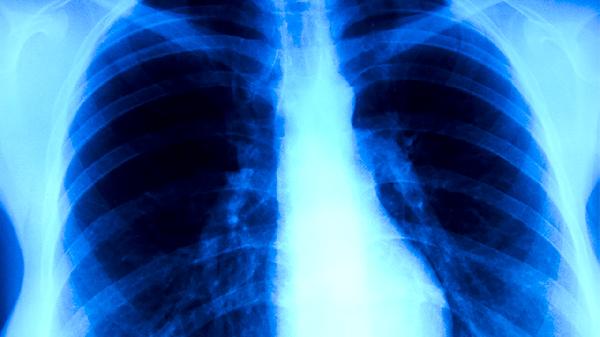

肺结核治愈后遗留的胸膜粘连是常见原因。结核病灶愈合过程中,胸膜组织可能发生纤维化粘连,在呼吸或体位变动时牵拉周围神经引发隐痛。此类疼痛多为间歇性钝痛,可通过局部热敷或适度拉伸缓解。

部分患者因结核病灶侵犯肋间神经或胸壁肌肉,即使痊愈后仍可能遗留神经敏感。疼痛表现为针刺感或烧灼感,尤其在疲劳或受凉时明显。维生素B族营养神经或中医针灸可能有帮助,但需排除其他器质性疾病。

日常需避免剧烈运动或突然扭转胸廓的动作,保持规律作息以降低疼痛发作频率。若疼痛持续超过两周、夜间加重或伴随体重下降,应进行胸部CT及结核菌素试验排查活动性结核。康复期可适当补充优质蛋白和维生素A、D,促进受损组织修复。